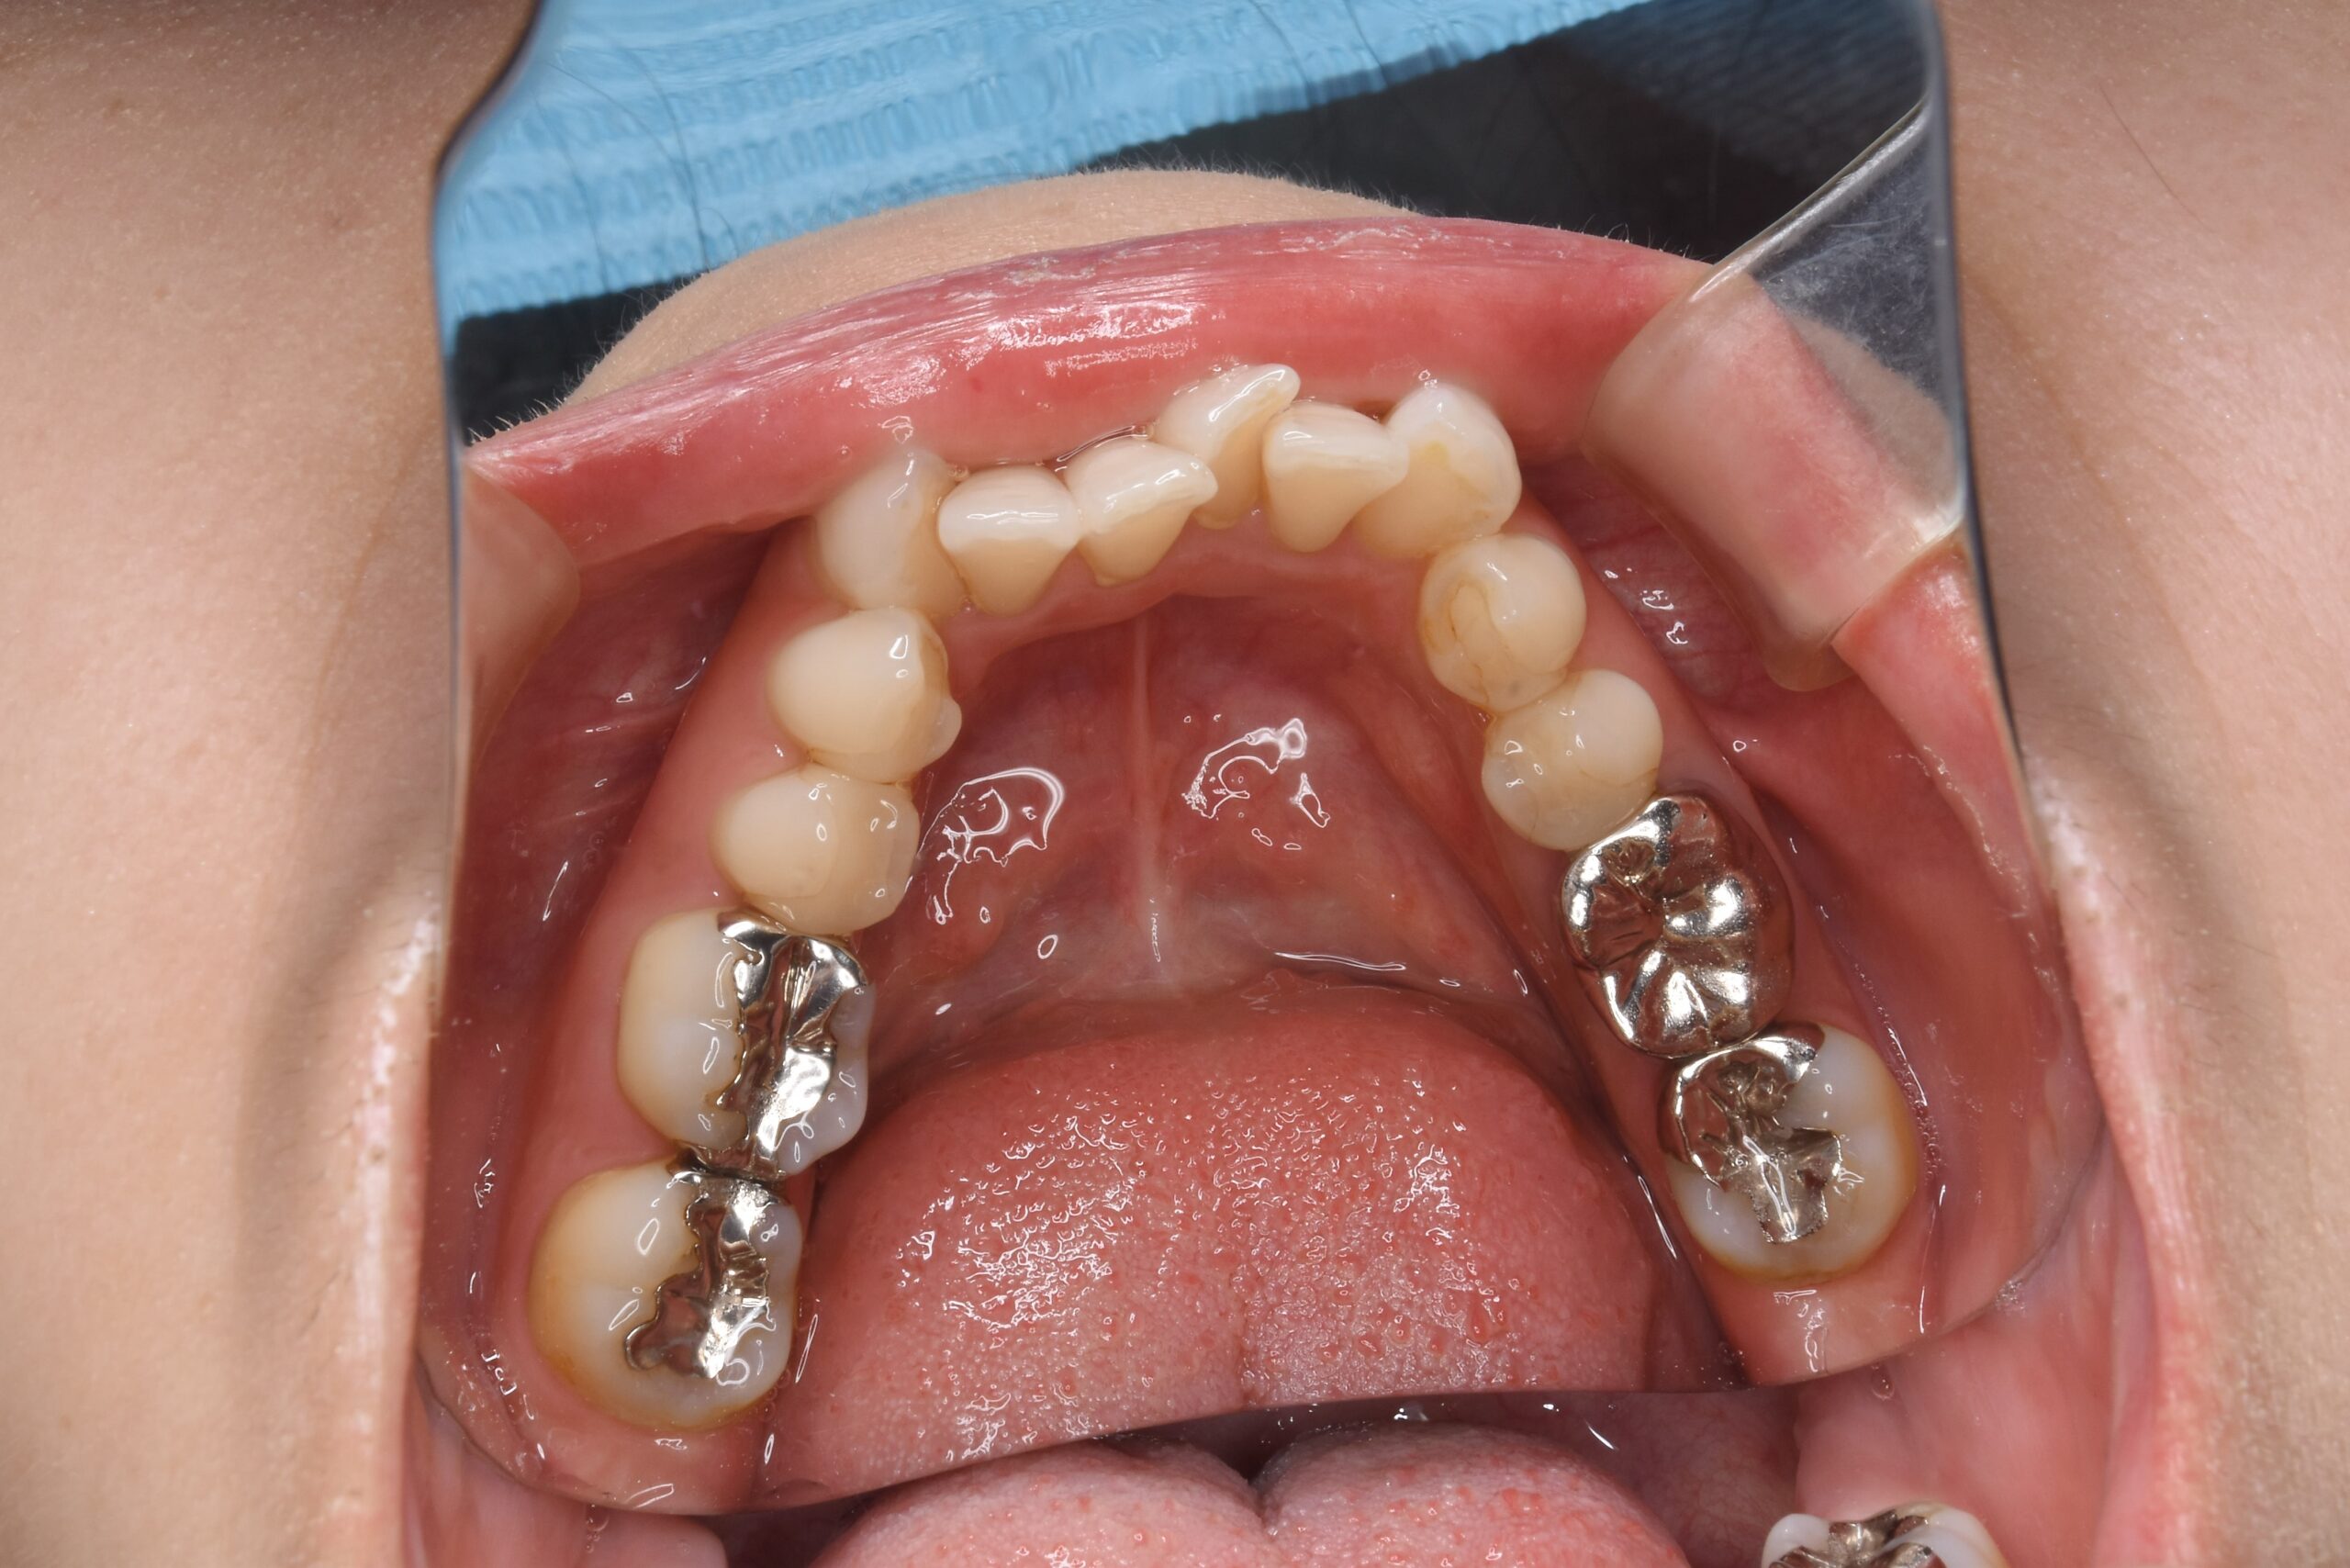

金属が気になる 30代 女性 セラミックインレーの症例

Before

診断 不適合補綴物

処置内容 セラミックインレー

処置回数 4回

治療費用 セラミックインレー1歯:5.5万円(税込み)

3歯

計 16.5万円